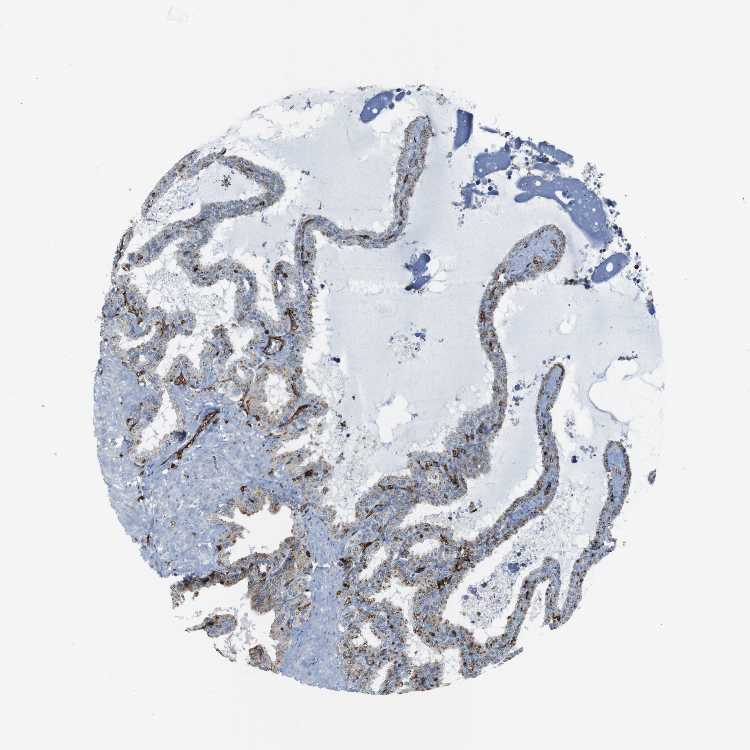

TISSUE PRIMARY DATA SEMINAL VESICLE Show tissue menu

SEMINAL VESICLE - Antibody stainingi

Antibody staining in the annotated cell types in the current human tissue is reported as not detected, low, medium, or high, based on conventional immunohistochemistry profiling in selected tissues. This score is based on the combination of the staining intensity and fraction of stained cells.

Each image is clickable and will lead to virtual microscopy that enables deeper exploration of all samples and also displays staining intensity scores, fraction scores and subcellular localization as well as patient and tissue information for each sample.

Antibody HPA050162Antibody HPA053176Antibody CAB015402

Glandular cells MediumMediumMedium